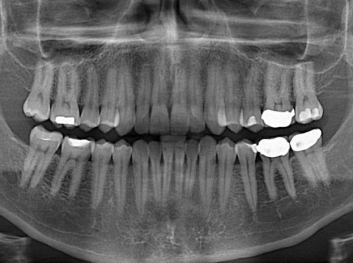

哈佛大學(xué):新型生物材料讓牙齒再生 來源: 南京泰盛生物科技有限公司 發(fā)布時間:2018-04-10

損壞的牙齒如何自我修復(fù)?近日,來自哈佛大學(xué)和諾丁漢大學(xué)的研究人員研發(fā)了能夠刺激牙齒干細胞再生的新型生物材料,而這種新材料研發(fā)成功的背后,正源于他們對牙齒如何實現(xiàn)自我修復(fù)這個課題的不斷探索。

據(jù)美國期刊《大眾科學(xué)(Popular Science)》報道,此種新型生物材料,不僅可以有效地取代傳統(tǒng)補牙填充物,刺激牙齒干細胞再生,患者也有望無需再接受根管治療,使蛀牙患者免除牙根感染或牙髓壞死的苦惱,一個全新的牙齒治療時代即將來臨。

Adam Celiz,是來自諾丁漢大學(xué)的研究人員,他和同事開發(fā)的這種新型合成生物材料,能刺激干細胞在牙髓部的生長。與普通材料一樣,這種合成材料被填充到牙齒并用UV光硬化。

在體外測試中,材料刺激干細胞進入牙本質(zhì)的增殖和分化速度,促進形成牙齒骨組織。研究人員認為,一旦材料在受損牙齒中應(yīng)用,這些干細胞可以自動修復(fù)來自填充物上的損壞。在本質(zhì)上,該生物材料將使牙齒自愈。

在未來,Adam Celiz說,可再生材料能制成各種填充物以便受損牙齒的自身治愈,降低補牙失敗率,甚至?xí)蟛糠秩藢Ω苤委煹男枰?/p>